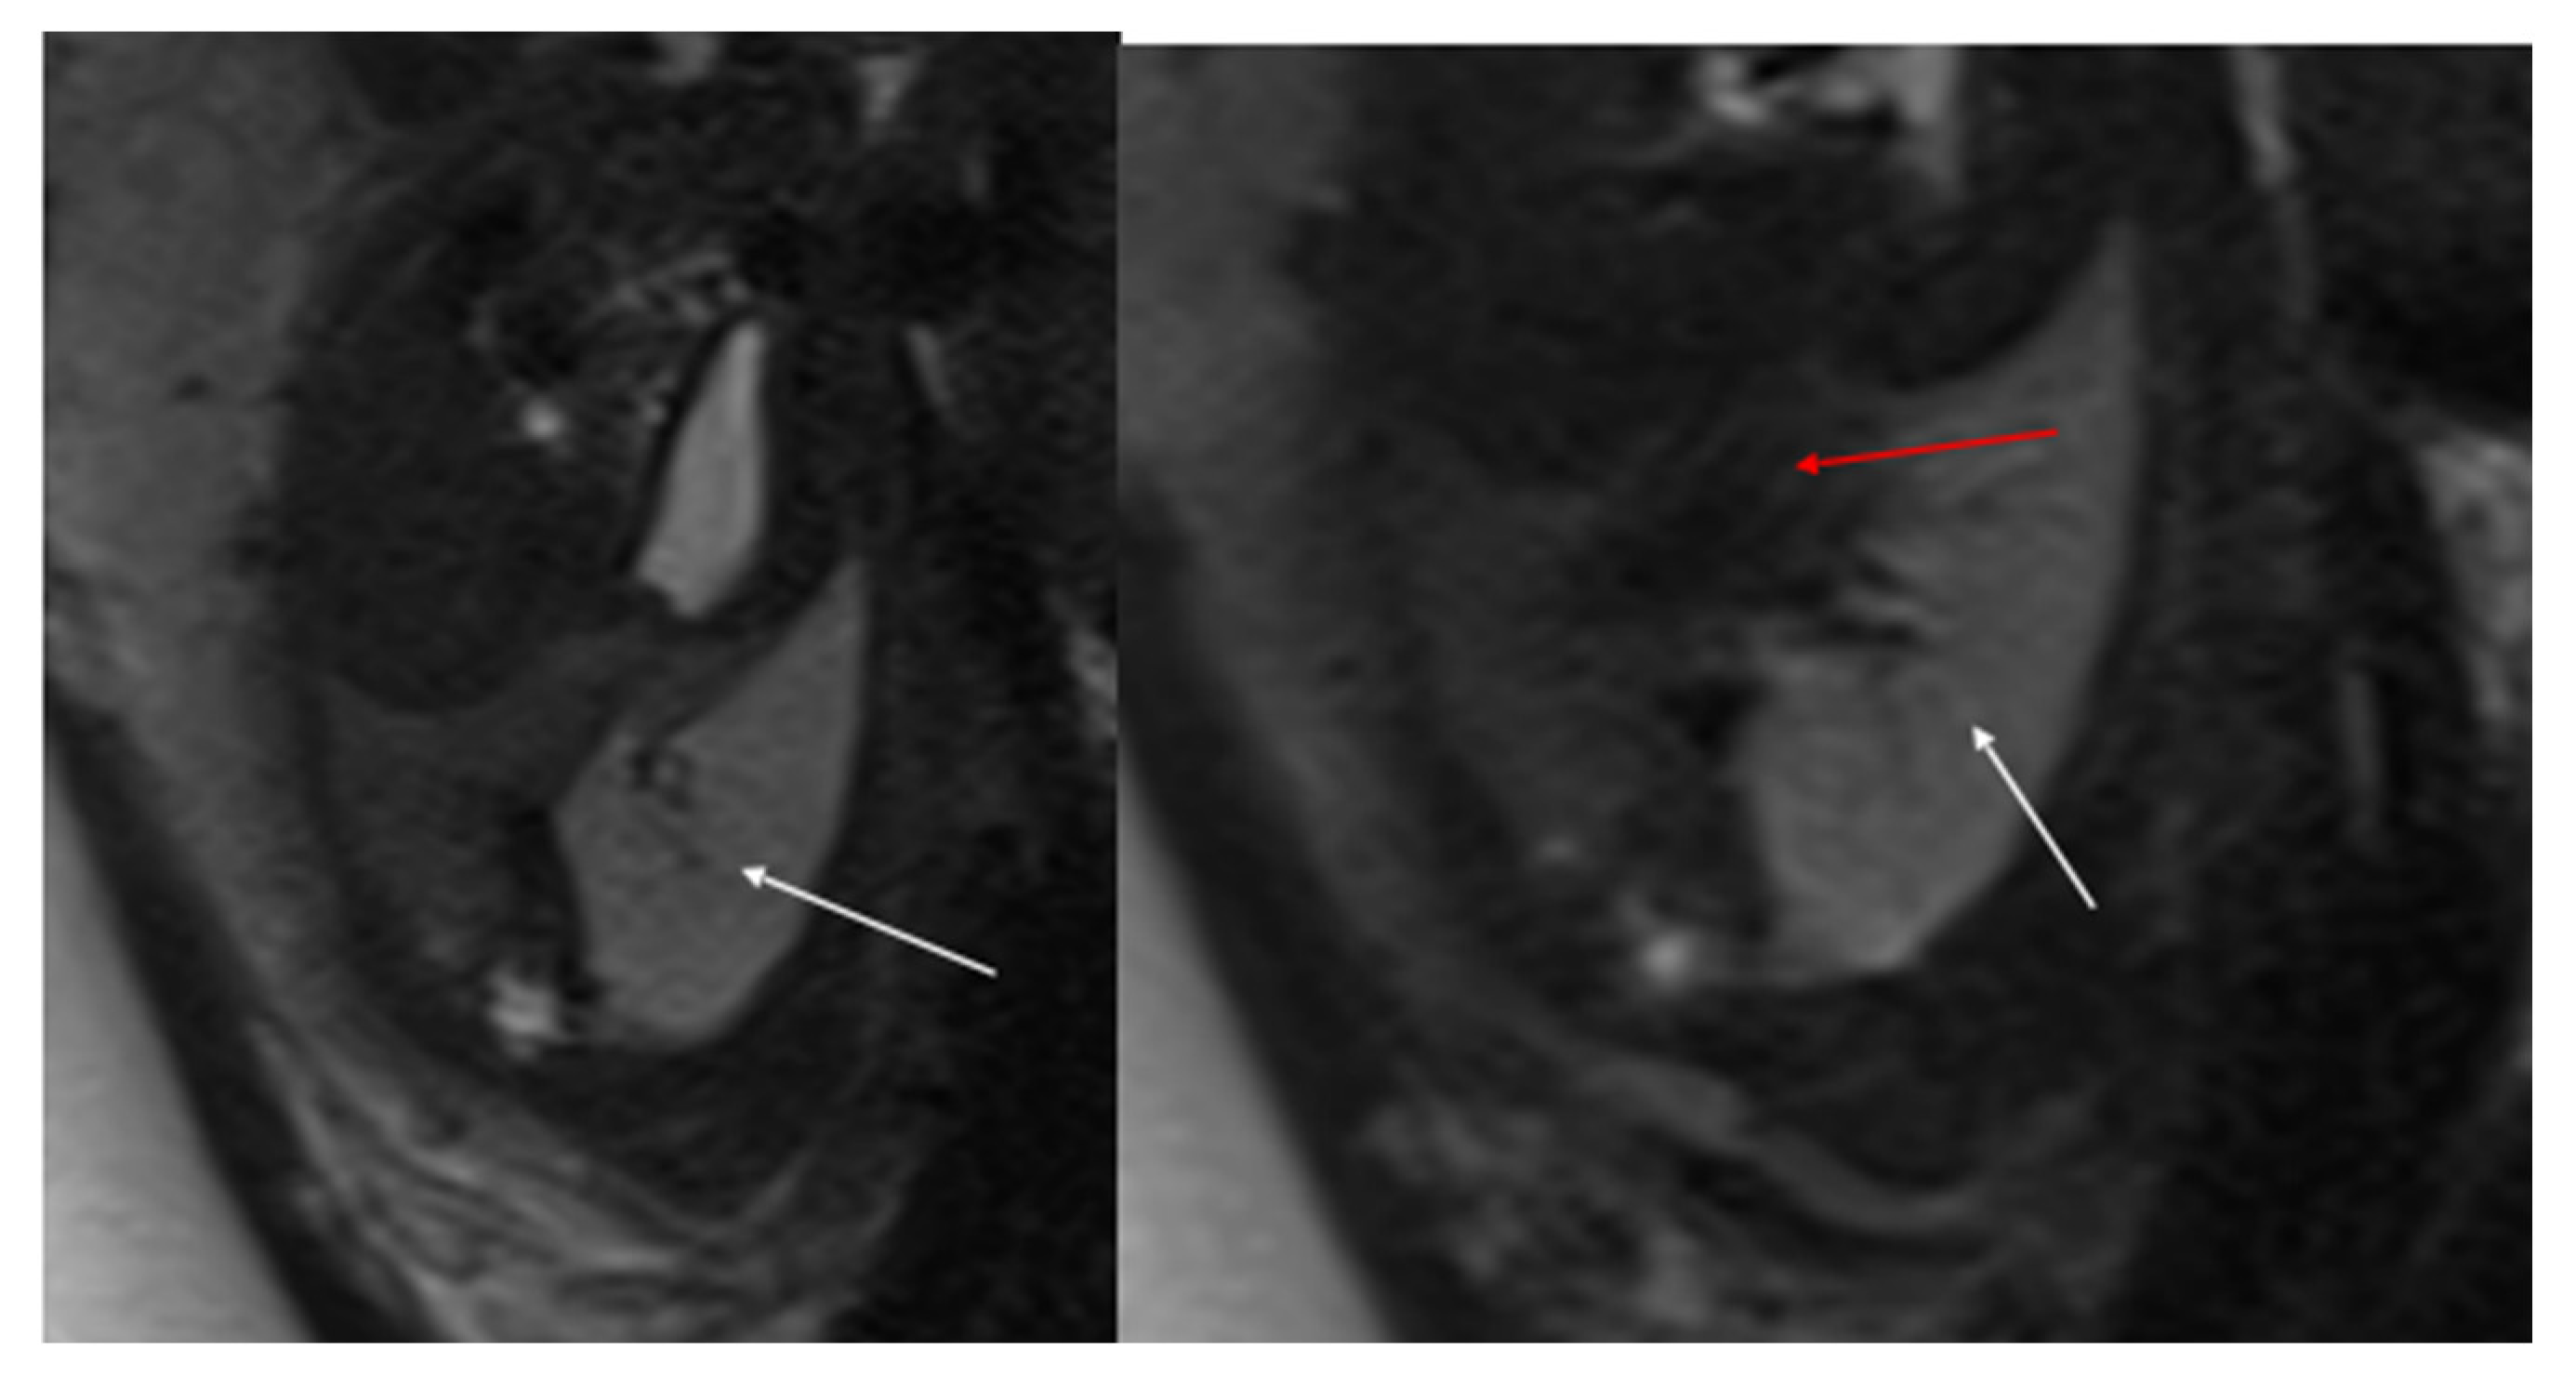

Figure 2. CPAM type II. Axial HASTE T2 MR images show a hyperintense lesion characterized by at least six cystic images (red arrow) of 2–6 mm at the lung base, with extension to the right posterior lung (orange arrow). No compression on the diaphragm or mediastinum. Minimal pleural effusion layer (white arrow).